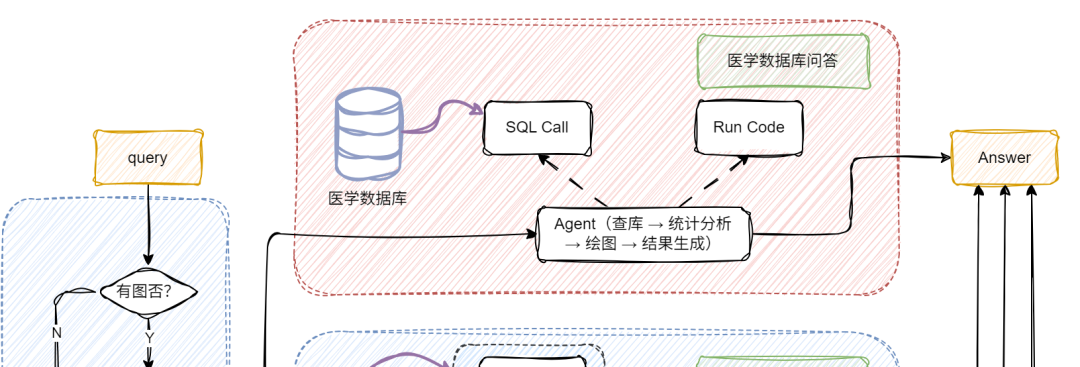

通过前面的探索,我们已经了解了朴素 RAG 如何让大模型具备“查资料再回答”的基础能力,也见证了多模态 RAG 通过图文融合实现的“感官升级”。但当实际应用场景涉及“医院年度病例统计分析”、“科研文献数据可视化呈现”等需求时,单纯的多模态处理仍显不足 —— 这类场景既需要解析医学影像、病历文本等非结构化数据,又要对接数据库完成指标计算、图表生成等 BI任务。

如何让 RAG 系统同时驾驭多模态理解与结构化数据分析?接下来要展开的多模态 + BI复杂架构实战,正是为解决这类“既要又要”的高阶需求而生,我们将在朴素 RAG 基础上层层叠加关键模块,最终打造出能同时处理影像诊断、数据统计、图表生成的全能型 AI 助手!

当用户提问中包含图片时,系统会自动触发 VQA,对图像进行结构化信息提取,挖掘上下文关键内容;若没有图像,就跳过这步,直接进入文本处理环节,效率UPUP!

接下来,系统通过意图识别模块,将不同类型的问题智能分流:

📌论文问答? 走传统 RAG 路线!向量检索+大模型生成,精准提取相关文献内容。

📌统计问答? 开启 SQL 模式!从提问中抽取结构化信息(如指标、维度、过滤条件),自动生成 SQL 查询,查询结果再由大模型“翻译”成自然语言,一目了然!

Agent 全流程 —— 数据分析 + 图表生成,一步到位

我们还基于 SQL Call 构建了一个全能型 Agent,具备:

📌数据库查询 → 数据分析 → 图表生成 → 结果汇总 的完整能力闭环。

也就是说,用户只需一句问题,Agent 就能自动完成整个流程,从查数到出图,一条龙服务!

首先定义两个工具(Tool),分别用于 SQL 查询 和 代码执行,并将它们作为可选工具提供给 Agent,支持其在执行任务过程中完成数据库查询和统计分析。这两个工具配合使用,使 Agent 能够动态完成从数据获取到分析执行的全流程任务。